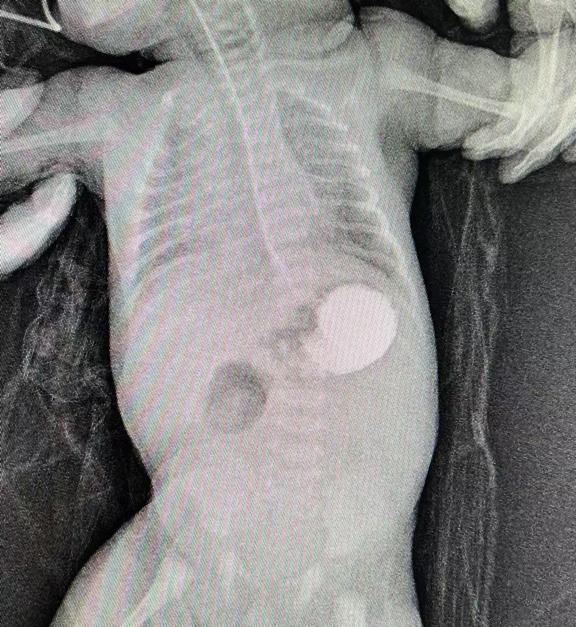

分娩將至,陳女士來到衡陽市中心醫(yī)院待產(chǎn)。醫(yī)院高度重視,組織多學(xué)科聯(lián)合會診,確定分娩方式,嚴(yán)密觀察產(chǎn)婦情況。1月11日下午,陳女士足月剖產(chǎn)一名3.44KG的男嬰,出生后頻繁嘔吐,隨即轉(zhuǎn)入新生兒科進(jìn)行監(jiān)護(hù)。主管醫(yī)生許承輝立即給患兒下胃管進(jìn)行胃腸減壓、全靜脈營養(yǎng),同時(shí)進(jìn)行上消化道造影檢查,進(jìn)一步明確了患兒十二指腸閉鎖的診斷。隨即新生兒科主任雷明、副主任王紅燕立即組織MDT聯(lián)合診治,制定最佳手術(shù)方案,充分術(shù)前評估,完善術(shù)前準(zhǔn)備。

術(shù)前造影提示十二指腸遠(yuǎn)端閉鎖